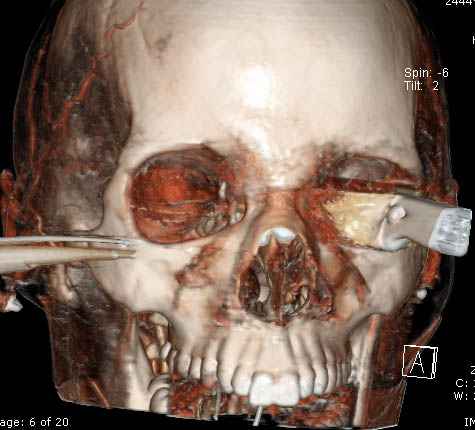

В своих выступлениях я рассказывал, что наши центры в мирное время по пенетрирующим травмам не уступает Ираку или Афганстану, и вот недавно к нам поступила больная 22 лет, травма "ножом в глаз" от бывшей подруги нынешнего "бой френда".

При поступлении в сознании, жаловалась на неприятные ощущения в глазнице.

По протоколу сделаны все необходимые исследования: рентген, ангиограмма с 3Д реконструкцией, где обнаружили что все жизненно важные сосуды не задеты, даже некоторые "сидят" изгибаясь на ноже.

Одним махом нож удалить не удалось, пришлось раскачать и потом двумя руками удалили нож. Рана без кровотечения, обработана и зашита.